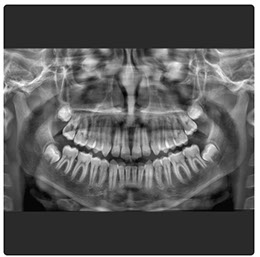

El Eagle 2D Pan/Tele ofrece todos los exámenes en el perfil panorámico (panorámica estándar, senos maxilares, baja dosis, bitewing, ATM, ortogonalidad perfeccionada, panorámica infantil y bitewing ortogonalidad perfeccionada) y todos los exámenes en el perfil cefalométrico (Posteroanterior, Antero-posterior, 45 Grados, Lateral, Carpal, PA de Walters, Axial Bazal, Hirtz).

La línea Eagle ofrece alta calidad de imagen, facilidad de operación, fácil posicionamiento del paciente y reúne lo mejor de la tecnología mundial en todas las funciones. El generador de rayos X de alta frecuencia reduce la exposición innecesaria del paciente. El sistema de microprocesado de alta velocidad y la mecánica precisa permiten la perfecta ejecución y repetición en imágenes 2D y 3D

Radiografía Panorámica Digital

Radiografía Panorámica